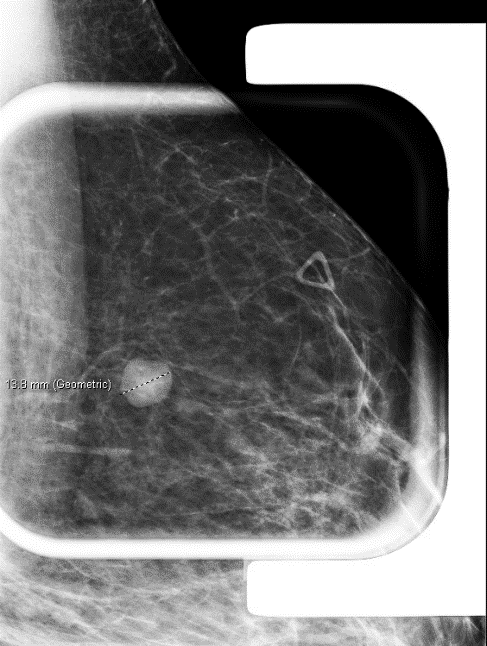

Case History

A 32-year-old female with a left breast suspicious mass at 12:00 o’clock underwent a needle biopsy.

What is the most likely diagnosis?

Answer A. Granular cell tumor